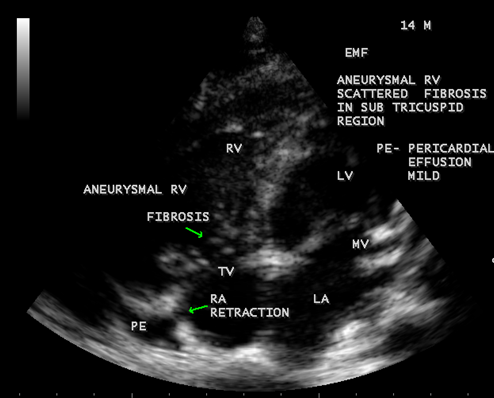

Figure 42: Endomyocardial fibrosis showing subtricuspid fibrosis, aneurysmal right ventricle, mild pericardial effusion and right atrial notch (RA retraction) in a 14-year old male.

Today echocardiography is used as the screening tool at the community level as the diagnosis of EMF could be confirmed at the bedside. Echocardiography accurately assesses the pathological abnormalities of chronic disease and it is the gold standard technique for the diagnosis of EMF [36]. It reveals dense endomyocardial echocardiograms along different parts of the mural and valvular endocardium and AV valve dysfunction [37] as shown in Figures 3 to 44. The typical feature of EMF is the obliteration of trabecular portion of the ventricle and in advanced cases, there is shrinkage of the cavities creating an apical notch, regurgitation, slow flow with spontaneous echo contrast as in Figure 36 and considerable pericardial effusion. Similar to apical notch of right ventricle, a right atrial notch is well seen as contraction (or retraction) of tricuspid annulus as in Figure 40 and right atrial notch as in Figure 41 and 42, indicating the retraction of rightatrial cavity as a peculiar feature of right ventricular EMF. Biventricular enlargement as shown in Figure 40 and biatrial enlargement as in Figure 32 are the characteristic features of advanced stage of EMF. The fibrosed muscular trabeculae extending into the cavities from the walls of the chambers in the right ventricle visible as ‘cobra heads’ as in Figure 4 and in pericardial sac as in Figure 29, in the left ventricle. Aneurysmal right ventricle with scattered areas of fibrosis in the sub tricuspid region and a notch in the right atrium is well seen in a 14 –year old boy as in Figure 42 . Right atrial notch is frequently noticed in EMF patients as shown in Figure 41 in a 47- year old male with left ventricular EMF and moderate pericardial effusion.